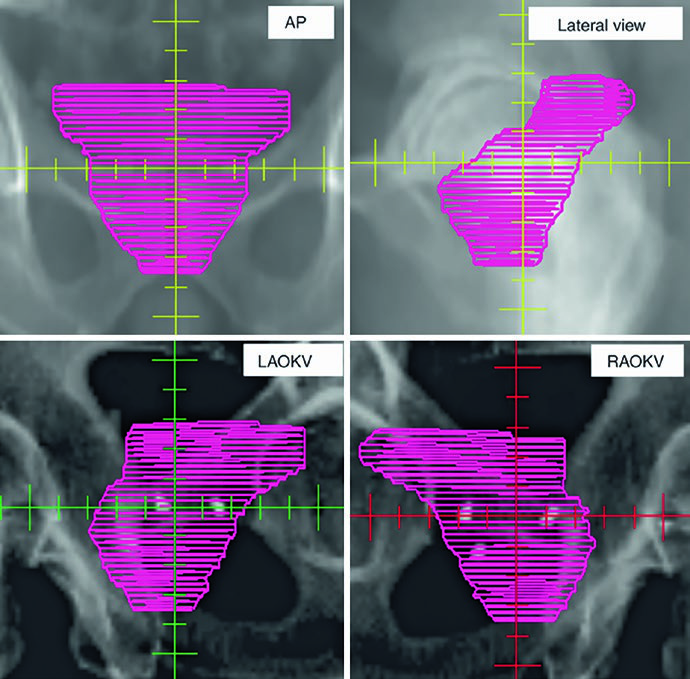

As figuras ajudam a entender por que o capítulo insiste na checagem 3D. A Fig. 25.1 mostra a sequência axial de um planejamento definitivo com TC de 2 mm fundida à RM T2, começando nas vesículas seminais e descendo até o ápice. A legenda chama atenção para o espaçador retal de hidrogel, melhor visto na RM T2, e cita o trabalho de Atluri sobre o uso de contraste iodado para facilitar a delimitação do espaçador mesmo sem apoio de RM. Já a Fig. 25.2 projeta o CTV em vistas AP, lateral e oblíquas. Ali fica claro o formato globular da glândula sob uma estrutura superior alada correspondente às vesículas seminais. Se o contorno avançar demais para o diafragma urogenital, a projeção inferior denuncia o erro rapidamente.

A Fig. 25.4 aprofunda esse ponto ao projetar o PTV em vistas ortogonais. Diferentemente do plano para próstata intacta, o pós-operatório inevitavelmente aproxima o volume da bexiga e do reto para cobrir possíveis focos microscópicos, incluindo o espaço perirretal anterior, a anastomose vesicouretral e os novos planos criados entre bexiga posterior, assoalho pélvico e VUA. A legenda destaca a sobreposição do PTV com reto em verde e bexiga em amarelo. A inspeção 3D garante que o limite anterior do PTV afile de forma progressiva acima da sínfise púbica. Quando essa transição fica abrupta, as mudanças diárias de enchimento vesical tornam o targeting mais suscetível a erro.